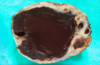

very common in the ovary, and originate from unruptured graafian collicles

cystic follicle

usually multiple, filled with serous fluid and lined by a gray glistening membrane, can be diagnosed by both palpation and US, may cause pain

cystic follicle in the ovary